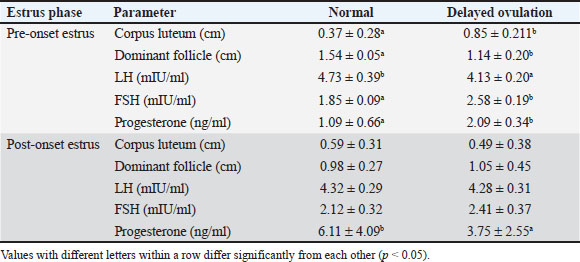

Table 2. Comparison of the diameter of the dominant follicle and corpus luteum and reproductive hormone concentration of Ongole crossbreed cows with and without delayed ovulation.

Hormone analysis

Hormonal analysis revealed that DO cows exhibited significantly lower LH levels during the pre-onset estrus phase compared with NO cows (4.13 ± 0.20 vs. 4.73 ± 0.39 mIU/ml, p < 0.05) (Table 2). This finding supports the role of elevated SBP in suppressing LH pulsatility and delaying the LH surge critical for ovulation. In contrast, FSH levels were higher in DO cows during pre-estrus (2.58 ± 0.19 vs. 1.85 ± 0.09 mIU/ml, p < 0.05), indicating that progesterone does not directly inhibit FSH secretion. Instead, the elevated FSH likely reflects a compensatory response to reduced negative feedback from estradiol due to smaller dominant follicles in DO cows. LH concentrations did not differ significantly between groups, while progesterone remained elevated longer in DO cows, consistent with delayed luteolysis and follicular dynamics.

Correlation analysis further demonstrated a strong negative relationship between LH and FSH levels during pre-onset estrus (r=−0.694, p=0.00), underscoring the differential regulation of these gonadotropins during DOO (Table 3). Progesterone was negatively correlated with FSH pre-estrus (r=−0.436, p=0.022), suggesting complex feedback interactions modulating FSH levels indirectly through estrogen rather than direct progesterone inhibition. These hormonal patterns align with ultrasound observations of smaller dominant follicles and larger retained corpora lutea in DO cows during pre-estrus, supporting the endocrine environment characterized by suprabasal progesterone suppressing LH release timing and amplitude, while FSH rises as a compensatory mechanism to altered estrogen feedback.